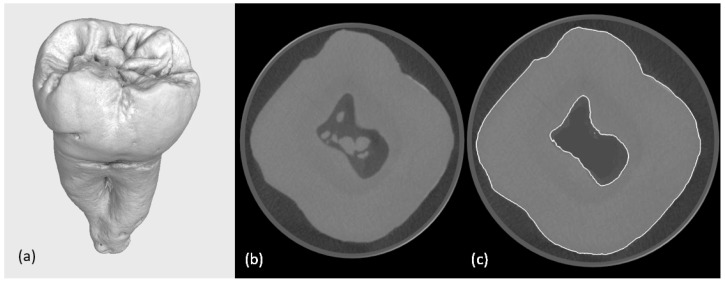

This study presents a methodology for developing and validating digital models of tooth-inlay systems, aiming to trace the complete workflow from clinical procedures to simulation by involving dental professionals-dentists for manual cavity preparation and dental technicians for restoration modelling-while integrating micro-computed tomography (micro-CT) imaging with finite element analysis (FEA). The proposed workflow includes (1) the acquisition of high-resolution 3D micro-CT scans of a non-restored tooth, (2) image segmentation and reconstruction to create anatomically accurate digital twins and mesh generation, (3) the selection of proper resin and the 3D printing of four typodonts, (4) the manual preparation of cavities on the typodonts, (5) the acquisition of high-resolution 3D micro-CT scans of the typodonts, (6) mesh generation, digital inlay and onlay modelling and material property assignment, and (7) nonlinear FEA simulations under representative masticatory loading. The approach enables the visualisation of stress and deformation patterns, with preliminary results indicating stress concentrations at the tooth-restoration interface integrating different cavity alternatives and restorations on the same tooth. Quantitative outputs include von Mises stress, strain energy density, and displacement distribution. This study demonstrates the feasibility of using image-based, tooth-specific digital twins for biomechanical modelling in dentistry. The developed framework lays the groundwork for future investigations into the optimisation of restoration design and material selection in clinical applications.